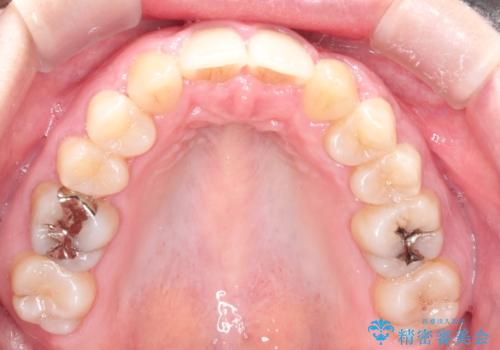

犬歯も通常の位置にまで移動することができ、口元もすっきりすることができました。

犬歯が変な位置にある 抜歯矯正により正しい位置へ

左上の犬歯が通常の位置より、かなり上方にあり、乳歯の残存と前歯のがたつきがありました。